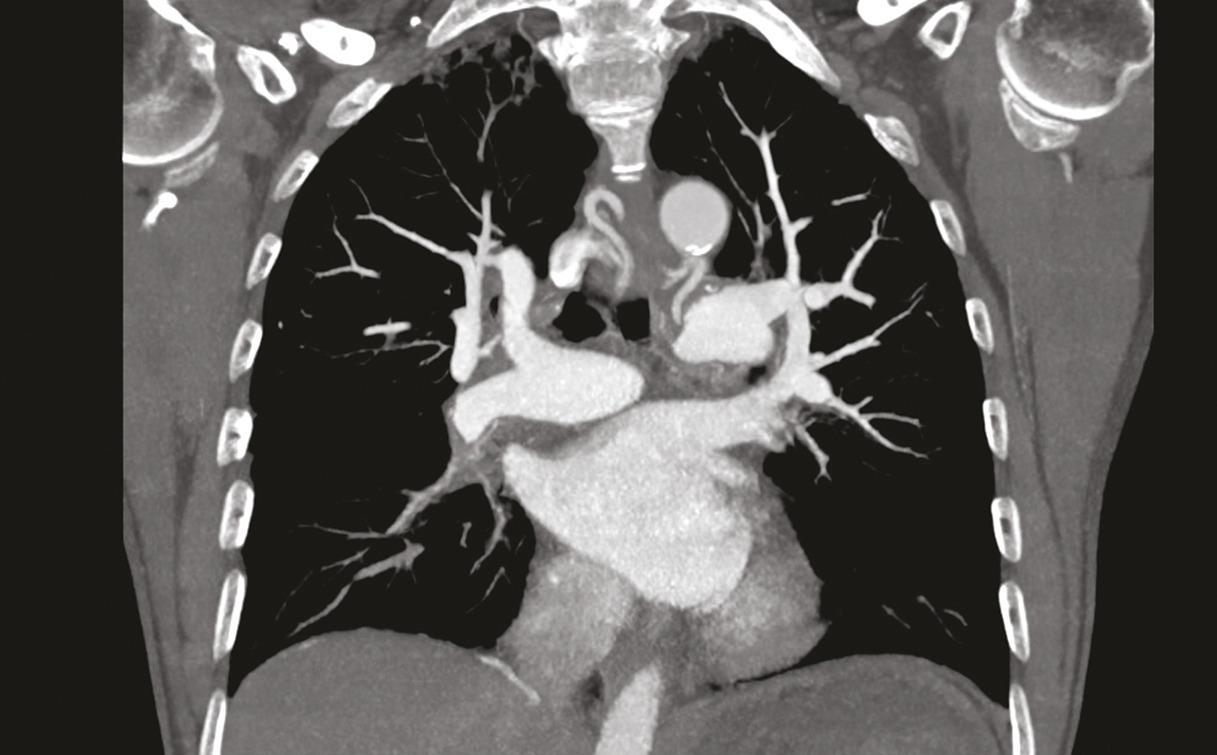

Dans le cas de monsieur M., l’embolie pulmonaire étant probable (en raison de l’antécédent de thrombose veineuse profonde et de la tachycardie à 115 batt/min), l’angio-TDM thoracique est réalisée d’emblée et confirme le diagnostic d’embolie pulmonaire proximale bilatérale (fig. 2) avec dilatation des cavités cardiaques droites et reflux dans la veine cave inférieure.

La prise en charge de l’hyper- tension pulmonaire thrombo- embolique chronique dépend de la localisation des séquelles thromboemboliques, proximale ou distale. Deux examens sont utiles à ce stade, l’angio-TDM thoracique (fig. 6) et l’angiographie pulmonaire (fig. 7).